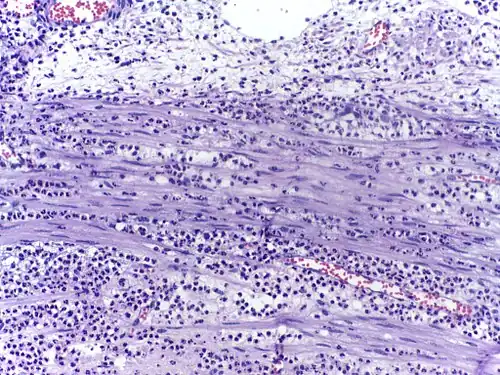

Воспалённые или повреждённые участки соединительной ткани требуют немедленной миграции разнообразных лейкоцитов, в том числе нейтрофилов, в очаг повреждения для удаления патогенных микроорганизмов и восстановления ткани. Наиболее хорошо процесс миграции в ткани изучен для нейтрофилов, которые прибывают в очаг воспаления первыми, существенно быстрее моноцитов, и способны развивать защитные метаболические реакции (в частности, «окислительный взрыв», сопровождающийся продукцией активных форм кислорода) в течение секунд. Активация нейтрофилов сопровождается в первую очередь высвобождением содержимого секреторных гранул. При развитии локального воспаления макрофаги, активированные бактериями или повреждениями ткани, выделяют провоспалительные цитокины, такие как IL-1 или фактор некроза опухоли α (TNF-α). Также к факторам хемотаксиса нейтрофилов относят компоненты комплемента, вещества, выделяемые тучными клетками, иммунные комплексы, эндотоксины и бактериальные пептиды, а также наполненные лизосомы, выходящие в ткань при распаде погибших нейтрофилов и макрофагов[33]. Под действием провоспалительных цитокинов в эндотелиальных клетках, выстилающих ближайшие к очагу воспаления посткапиллярные венулы, увеличивается количество селектинов на поверхности, обращённой в просвет сосуда. Нейтрофилы, циркулирующие в посткапиллярных венулах и имеющие подходящий набор поверхностных гликопротеинов, связываются с селектинами на поверхности эндотелиальных клеток. На данном этапе связывание с эндотелием непрочное, и нейтрофилы продолжают «катиться» по поверхности эндотелия. Провоспалительные цитокины запускают экспрессию интегринов в катящихся нейтрофилах и лигандов интегринов, известных как ICAM-1, на поверхностях эндотелиальных клеток. В то же время межклеточные контакты между клетками эндотелия ослабляются, и эндотелий становится более проницаемым. За счёт интегринов нейтрофилы прочно связываются с эндотелием и прекращают качение, и в конечном счёте приступают к прохождению через эндотелий с помощью псевдоподий (этот процесс известен как диапедез). Проникновение нейтрофилов через эндотелий облегчается благодаря длинному и сегментированному ядру. Прохождение нейтрофилов через эндотелий и дальнейшая миграция к очагу воспаления стимулируются хемокинами[34]. Базальные мембраны нейтрофилы преодолевают благодаря выделению содержимого желатиназных гранул[35].

Массовая миграция нейтрофилов в ткань при остром воспалении